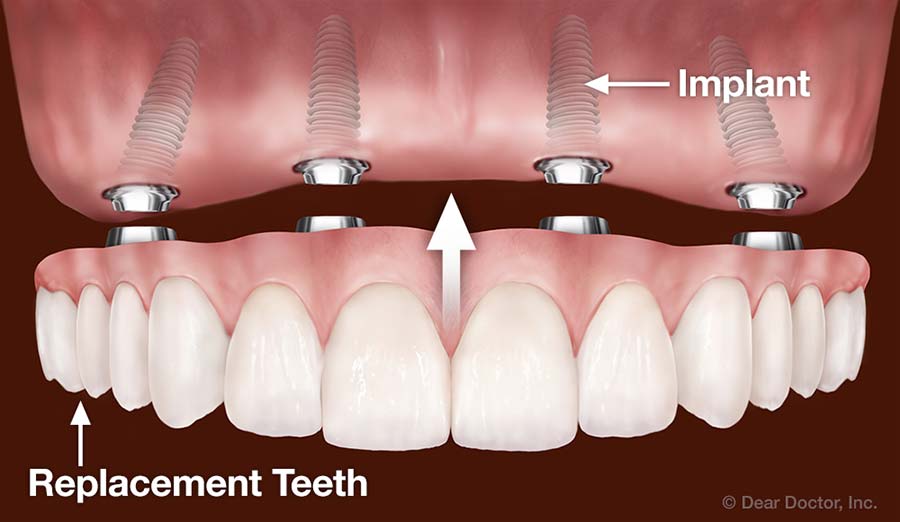

Do teeth implants look natural?

In addition, we can shape, grind and shape the crown to fit perfectly with the shape of the replaceable tooth – so yes, the implants offer a natural-looking replacement that looks and works just like a regular tooth. See the article : Dental Implants.